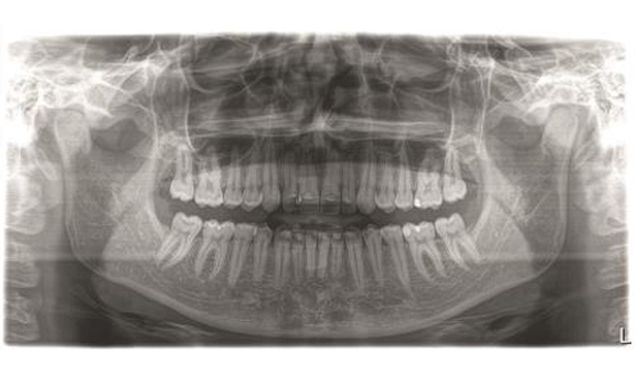

Sharp Layer technology is designed to produce sharp images and automatically adapts the panorama curve of the DCS to the patient’s individual anatomical situation, reportedly making it unnecessary to first select jaw morphology and front tooth position and thus simplifying the operation of the X-ray unit.

According to Jörg Haist, director of product management, imaging division, at Sirona, SL technology offers numerous other technical features that improve image quality to provide the best X-ray resolution on the market with ORTHOPHOS SL and win over dentists with high standards all over the world. It generates several thousand images from different angles during a single rotation, reportedly offering excellent panoramic images and the opportunity to correct positioning errors retroactively.

Furthermore, interactive Sharp Layer technology reportedly makes it possible to shift the depth of focus retroactively in the buccal-lingual direction so that in case of unclear overlays, it is immediately apparent which structure is in front and which is behind. It is also said to automatically combine fragments with the best focus to form a single radiographic image with incomparable sharpness.

“The new ORTHOPHOS SL combines two new technologies that enable high resolution images of anatomical structures at a low dose," he says.

He stresses that the DCS makes an especially efficient generation of imaging possible and points out that it is the addition of the reconstructive Sharp Layer process to the highly developed panoramic process that provides high contrast images for better diagnostics and treatment for patients.